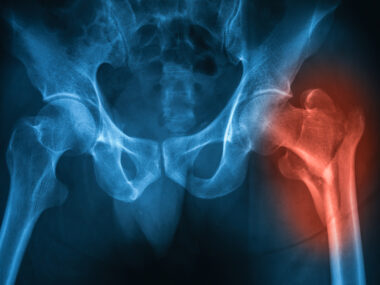

Ankylosing spondylitis (AS) patients undergoing total hip replacement face longer hospital stays and higher related costs than other patients after the surgery, according to an analysis of hospital records.

Many patients with AS-related hip damage require total hip replacement surgery, also called hip arthroplasty, which involves surgically removing damaged bone and cartilage, then replacing the hip with an artificial joint.

Analysis revealed that people with AS had a longer hospital stay on average after hip replacement compared with other patients (2.5 vs. 2.3 days), with a higher total cost of care ($72,950 vs. $66,872). No differences were seen between groups in the type of facility they were transferred to after leaving the hospital.

Overall, the complication rate was higher with AS patients than with controls. A significantly higher risk of developing infections related to the artificial joint (2.4% vs. 1.0%), a major complication of hip replacement surgery, occurred in AS patients. They also had significantly higher rates of anemia (21.8% vs. 11.8%) — a condition marked by low levels of healthy red blood cells.

The researchers then compared the two groups after matching individuals for pre-surgical factors, such as age, sex, obesity, diabetes, and tobacco use. Higher rates of anemia caused by blood loss were significantly higher in AS patients (21.76%) than in controls (15.89%). The most common local hip replacement complication in those with AS was an artificial joint-related infection (2.4% vs. 0.84%).